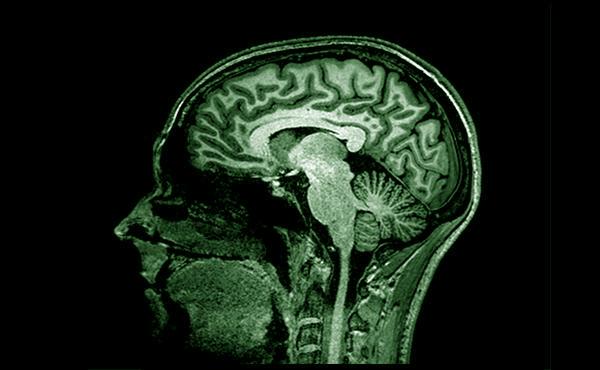

El Grup de Recerca en Neuroimatge se centra en l'estudi d’imatges cerebrals obtingudes amb ressonància magnètica (MRI) i tomografia per emissió de positrons (PET). Aquestes imatges permeten revelar canvis fisiopatològics associats a la malaltia d'Alzheimer i l'envelliment saludable que poden ser informatius de noves estratègies de prevenció. Amb aquesta finalitat, s'analitzen les dades de neuroimatge juntament amb la cognició, la genètica, els biomarcadors i altres factors clínics, ambientals i d'estil de vida per detectar el seu impacte en el cervell a nivell estructural, funcional i molecular. El Grup de Recerca en Neuroimatge està format per un equip multidisciplinari d'experts en adquisició, processament i anàlisi de dades complexes de neuroimatge.

Les tècniques de neuroimatge, com la ressonància magnètica i la tomografia per emissió de positrons, permeten caracteritzar les alteracions cerebrals en la fase preclínica de l’Alzheimer. Així, els investigadors poden millorar el coneixement dels processos fisiològics involucrats en la resposta a l’inici dels primers canvis patològics cerebrals.

Aquesta línia se centra en desenvolupar mètodes nous i més convenients per millorar la detecció d'alteracions fisiopatològiques en la malaltia d’Alzheimer. Amb aquesta finalitat, el grup desenvolupa noves seqüències de pols de ressonància magnètica que són sensibles als canvis associats a l'acumulació de proteïnes mal plegades al cervell.